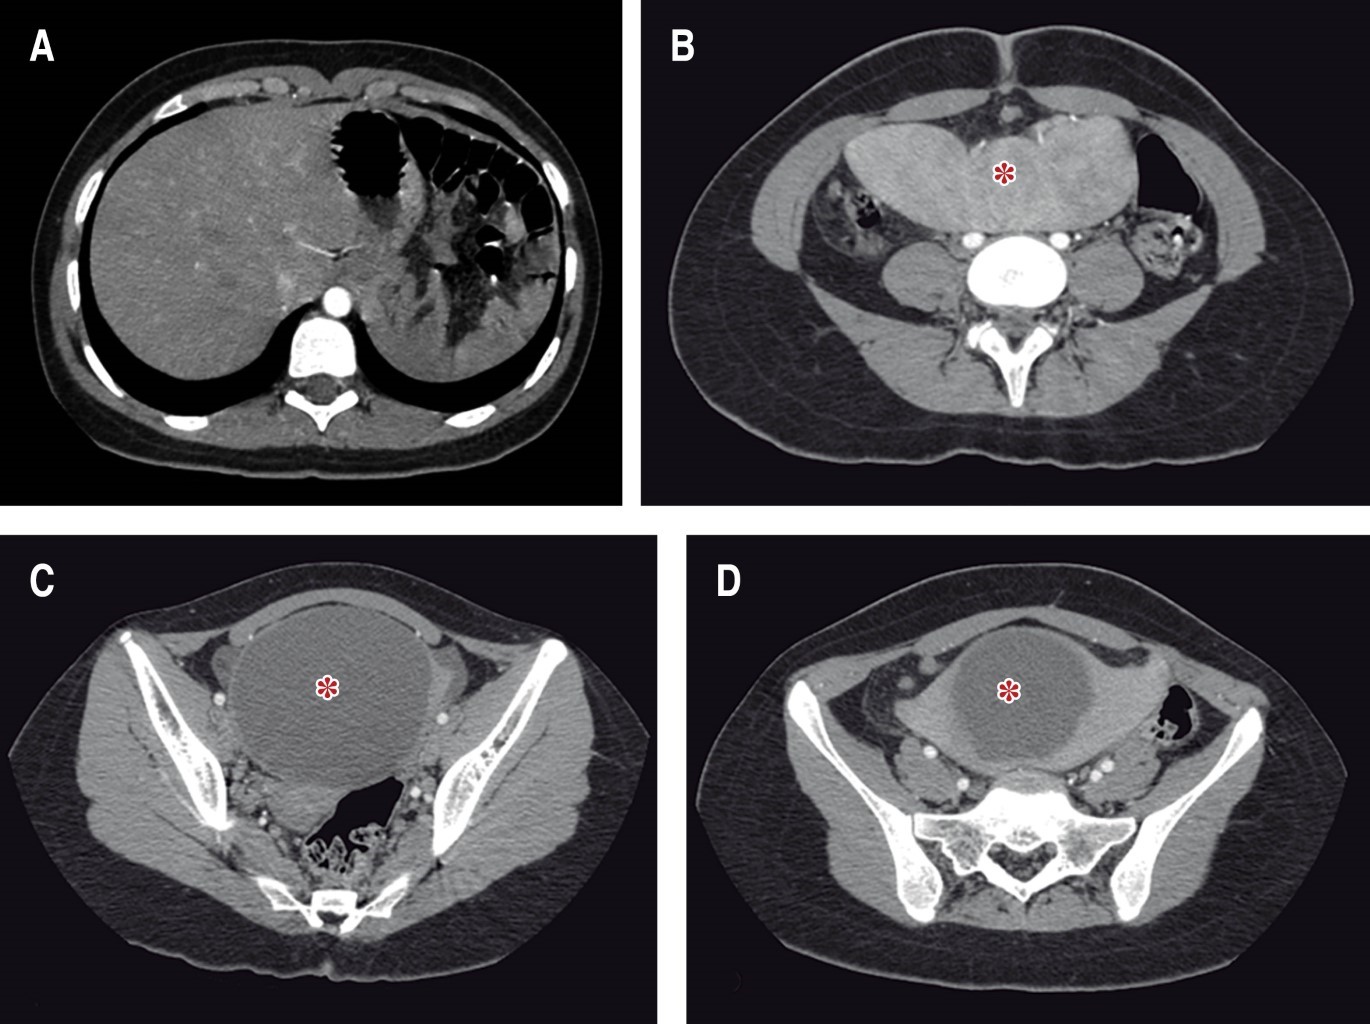

A la exploración física se logra palpar tumor delimitado, móvil, de aproximadamente 9 × 8 cm en cuadrante inferior izquierdo, sin datos de irritación peritoneal, se complementa abordaje con laboratorios en los que se reporta biometría hemática y química sanguínea dentro de parámetros normales, Ca-125 17 U/ml, tomografía abdominopélvica que reporta imagen compleja dependiente de ovario izquierdo (Figuras 1 y 2). Se decide realizar laparotomía exploradora electiva, donde se encuentra presencia de bazo errante a nivel pélvico con quiste de 9 × 9 cm (Figuras 3, 4 a 5), se realiza evisceración de bazo y drenaje de quiste, obteniendo 480 cm3 de contenido cetrino. Se solicita apoyo transoperatorio al Servicio de Cirugía General para la realización de esplenectomía, la cual se lleva a cabo con éxito. Útero, anexos y resto de vísceras sin alteraciones. Evolución postoperatoria adecuada, con egreso a las 24 horas de su ingreso, continuando con protocolo de paciente postesplenectomizado por externo.

El cuadro clínico cuando se presenta sintomático suele ser inespecífico, por lo que los estudios imagenológicos juegan un importante papel en el diagnóstico y de sus complicaciones. La tomografía abdominal contrastada es considerada el mejor estudio, aunque también pudiera ser útil el ultrasonido de abdomen. A menudo se identifica por su forma característica de "coma", sin observar el bazo en el cuadrante superior izquierdo; seguir el trayecto de los vasos esplénicos puede ayudar a identificar correctamente el bazo errante (Figuras 2 y 7).2